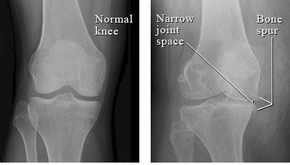

jeremiahpamerMar 11, 20236 min readThe Legend of King Arthur-itis and the Knights of the Trendelenburg’d Surgical Table